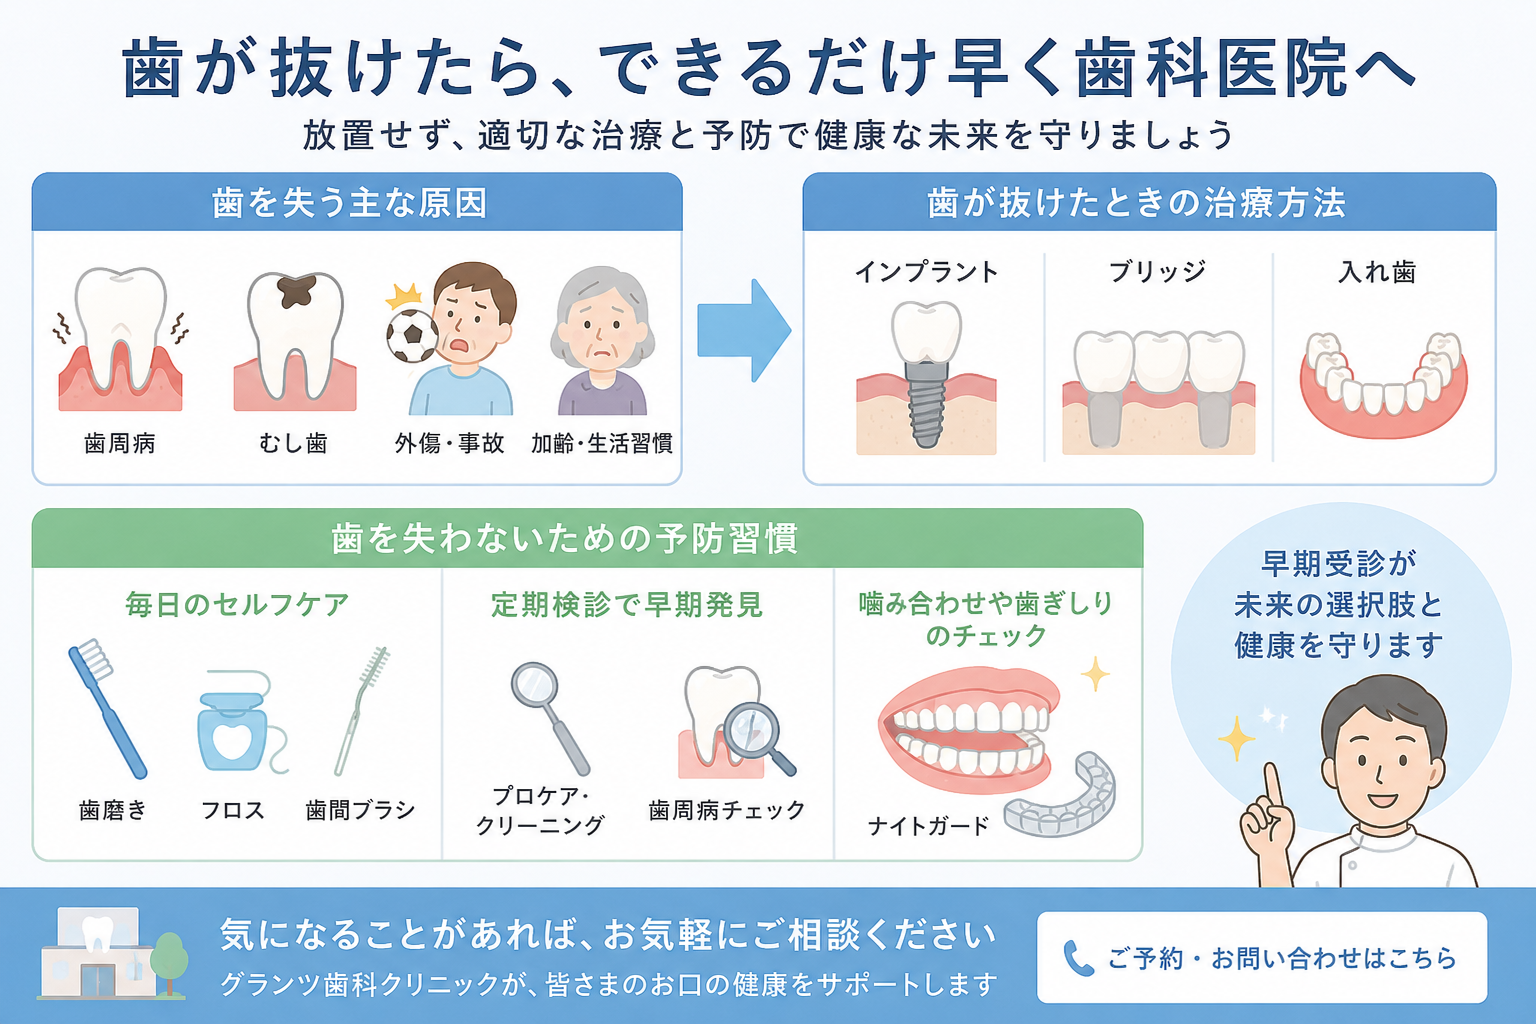

まずはお電話にてご相談ください。